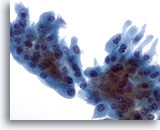

Figure 5

Breast FNA, Fibroadenoma.

A large branching sheet of cohesive, uniform benign ductal cells is seen overlying a stromal fragment. Note the small, somewhat spindled stromal cell nuclei within the stromal fragment. 20x

Figure 5

Breast FNA, Fibroadenoma.

A large branching sheet of cohesive, uniform benign ductal cells is seen overlying a stromal fragment. Note the small, somewhat spindled stromal cell nuclei within the stromal fragment.

20x